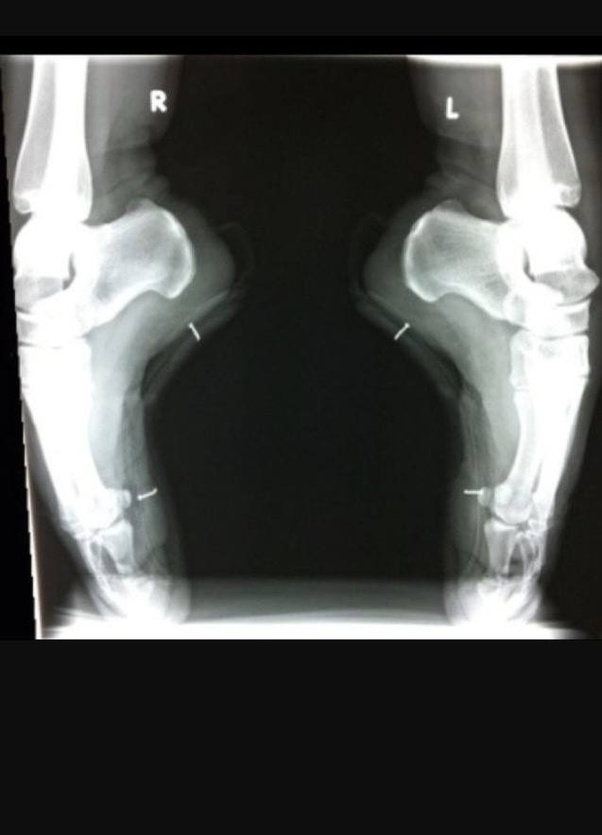

Ballerina Feet X-Ray

Ballerina feet XRay Interesting XRay picture of ballerina feet

Web ballerinas literally put their entire body weight on their big toes. Joining english national ballet and dancing in the chorus of.